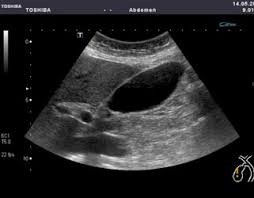

Si cet examen en temps réel est obligatoire chez la femme enceinte au moins trois fois selon l’Organisation mondiale de la santé (OMS), c’est-à-dire à chaque trimestre de la grossesse, il peut également tous nous concerner et peut être prescrit par le médecin pour faciliter le diagnostic de certaines maladies. En effet, elle permet l’étude de multiples organes de l’abdomen, du petit bassin et du cou (thyroïde, ganglions, foie, rate, pancréas, reins, vessie, organes génitaux) mais aussi les vaisseaux (artères et veines), les ligaments et le cœur. Elle recherche des anomalies qui pourraient les atteindre (tumeurs, infections, malformations) et peut parfois guider un prélèvement en profondeur. Les avantages de l’échographie sont bien connus : pas d’irradiation, pas de risque d’allergie, peu de contre-indications. Cet examen est rapidement réalisé, l’image est obtenue en temps réel. Il est indolore et peu couteux. Il peut être réalisé dans n’importe quel endroit via l’échographe portable. Cependant, l’un des inconvénients majeurs de l’échographie est qu’elle est opérateur-dépendant.

- Vésicule biliaire

- Foie en avant de rein droit